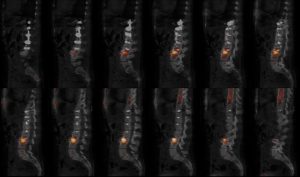

DMA sur arthrodèse thoraco-lombaire

Douleur mécanique lombaire chez une patiente aux antécédents d’arthrodèse thoraco-lombaire pour scoliose (>10ans).

Phase tissulaire : pas de foyer d’hyperhémie en regard du rachis lombaire ou du bassin.

Phase osseuse : discarthrose hyperfixante L3-L4.

Fracture de la tige d’arthrodèse au niveau de T12-L1 et fracture d’une vis au niveau de L2.

Lyse isthmique bilatérale de L5 non hyperfixante.

Discrète hyperfixation linéaire du sacrum en rapport avec la fissure ancienne connue.

Dégénérescence mécanique L3-L4 adjacente à l’arthodése thoraco-lombaire.

Fracture du matériel.